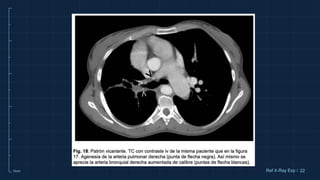

PATRÓN VASCULAR

VICARIANTE

Consiste en la visualización de la circulación arterial

bronquial en la radiografía simple de tórax, que en

condiciones normales no se identifica.

Patrón vicariante. Paciente con agenesia de la

arteria y venas pulmonares derechas y secuestro

pulmonar en lóbulo inferior derecho. A. Radiografía

simple de tórax PA. El pulmón derecho está

disminuido de volumen y en él se aprecia que su

vasculatura no sigue una distribución centrífuga y

arboriforme como en el pulmón contralateral. B.

Detalle de la radiografía anterior. La vascularización

pulmonar izquierda conforma una red

desorganizada, correspondiente a circulación

bronquial. C. Reconstrucción coronal en modo MIP

con ventana de pulmón de TC con contraste iv. Se

aprecia que la distribución de la vasculatura

pulmonar izquierda no sigue UN patrón arboriforme

como en el pulmón contralateral. D. Reconstrucción

coronal en modo MIP con ventana de mediastino de

TC con contraste iv. Se visualiza la arteria bronquial

derecha y una rama de la aorta toraco-abdominal

(puntas de flecha), la última responsable de la

irrigación del secuestro pulmonar.